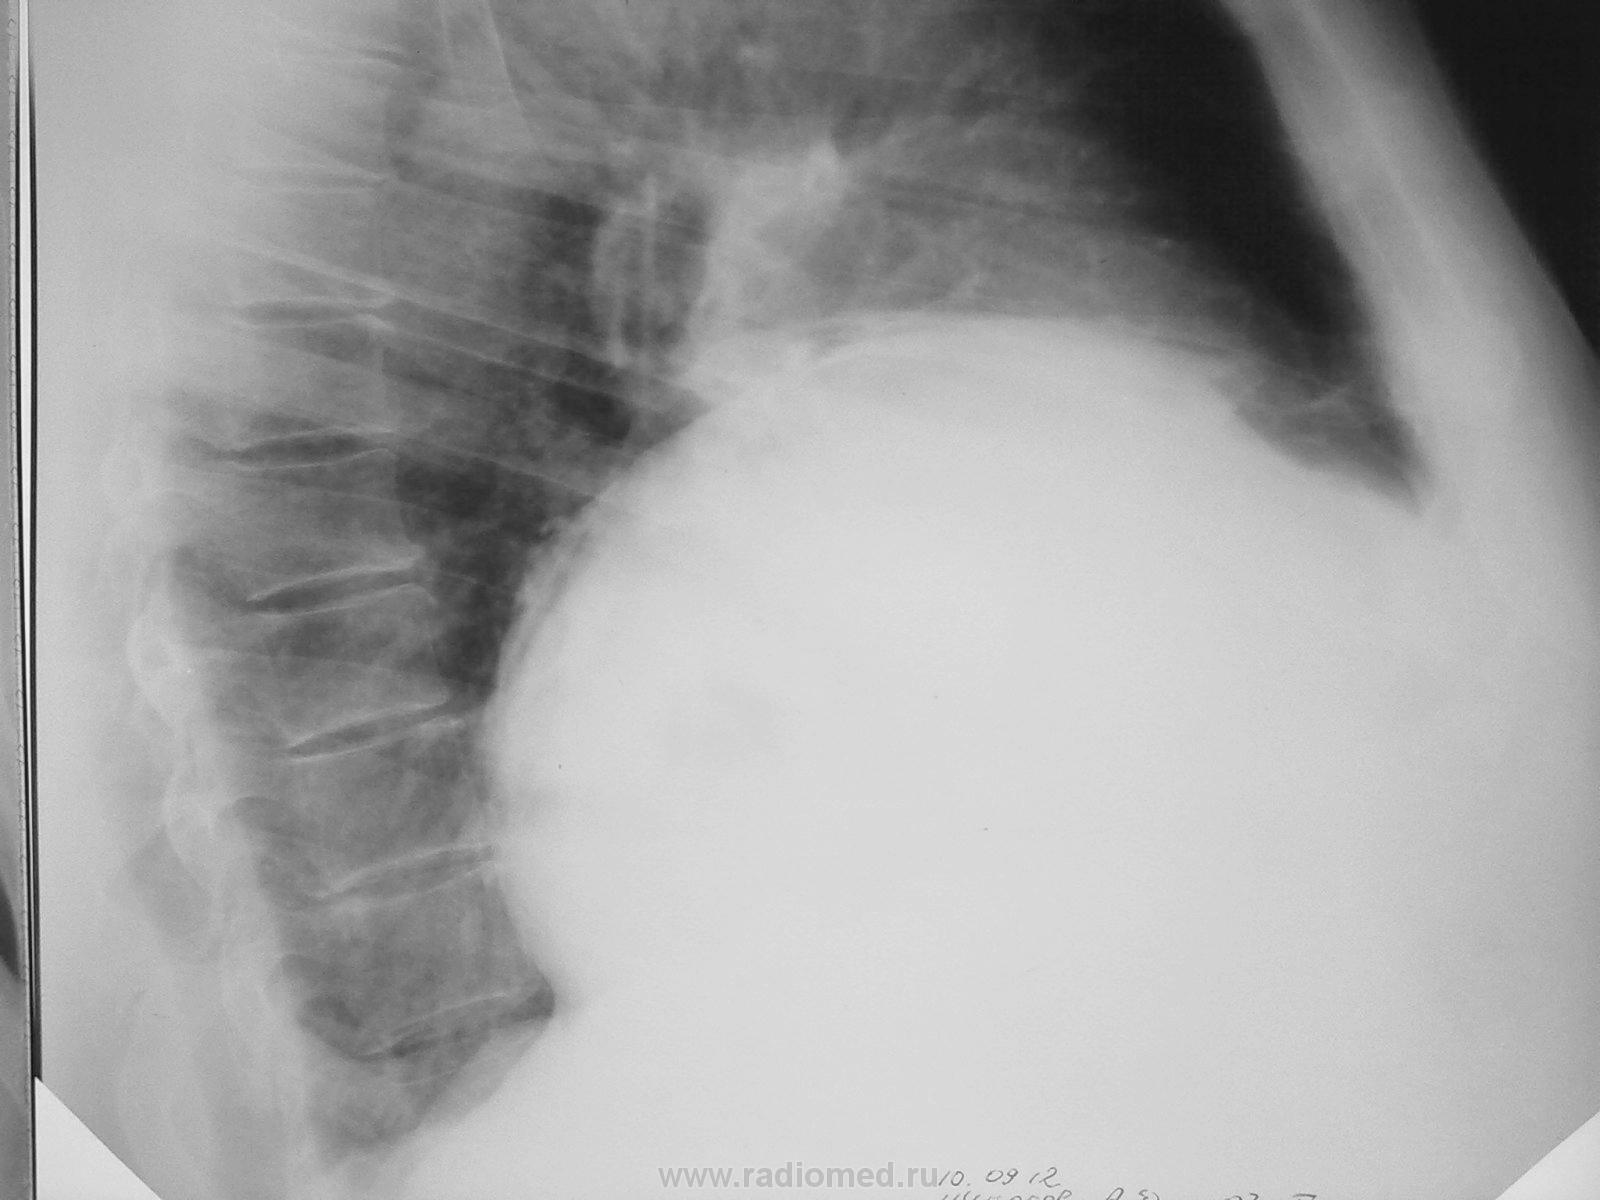

а как отдифференцировать методами классической рентгенологии осумкованный выпот от кисты в данном случае? КТ у нас в отпуске скопию стоя сделал, глоток бария дал, ничего нового не получил

Липома? Интересно, что на УЗИ в печени.

на узи в пределах возрастных изменений. липома? а не в переднем синусе она обычно бывает?

P.S. Эхинококк печени может.

спасибо за комментарии, про эхинококк и не думал, буду рекомендовать КТ

а как отдифференцировать методами классической рентгенологии осумкованный выпот от кисты в данном случае? КТ у нас в отпуске

скопию стоя сделал, глоток бария дал, ничего нового не получил